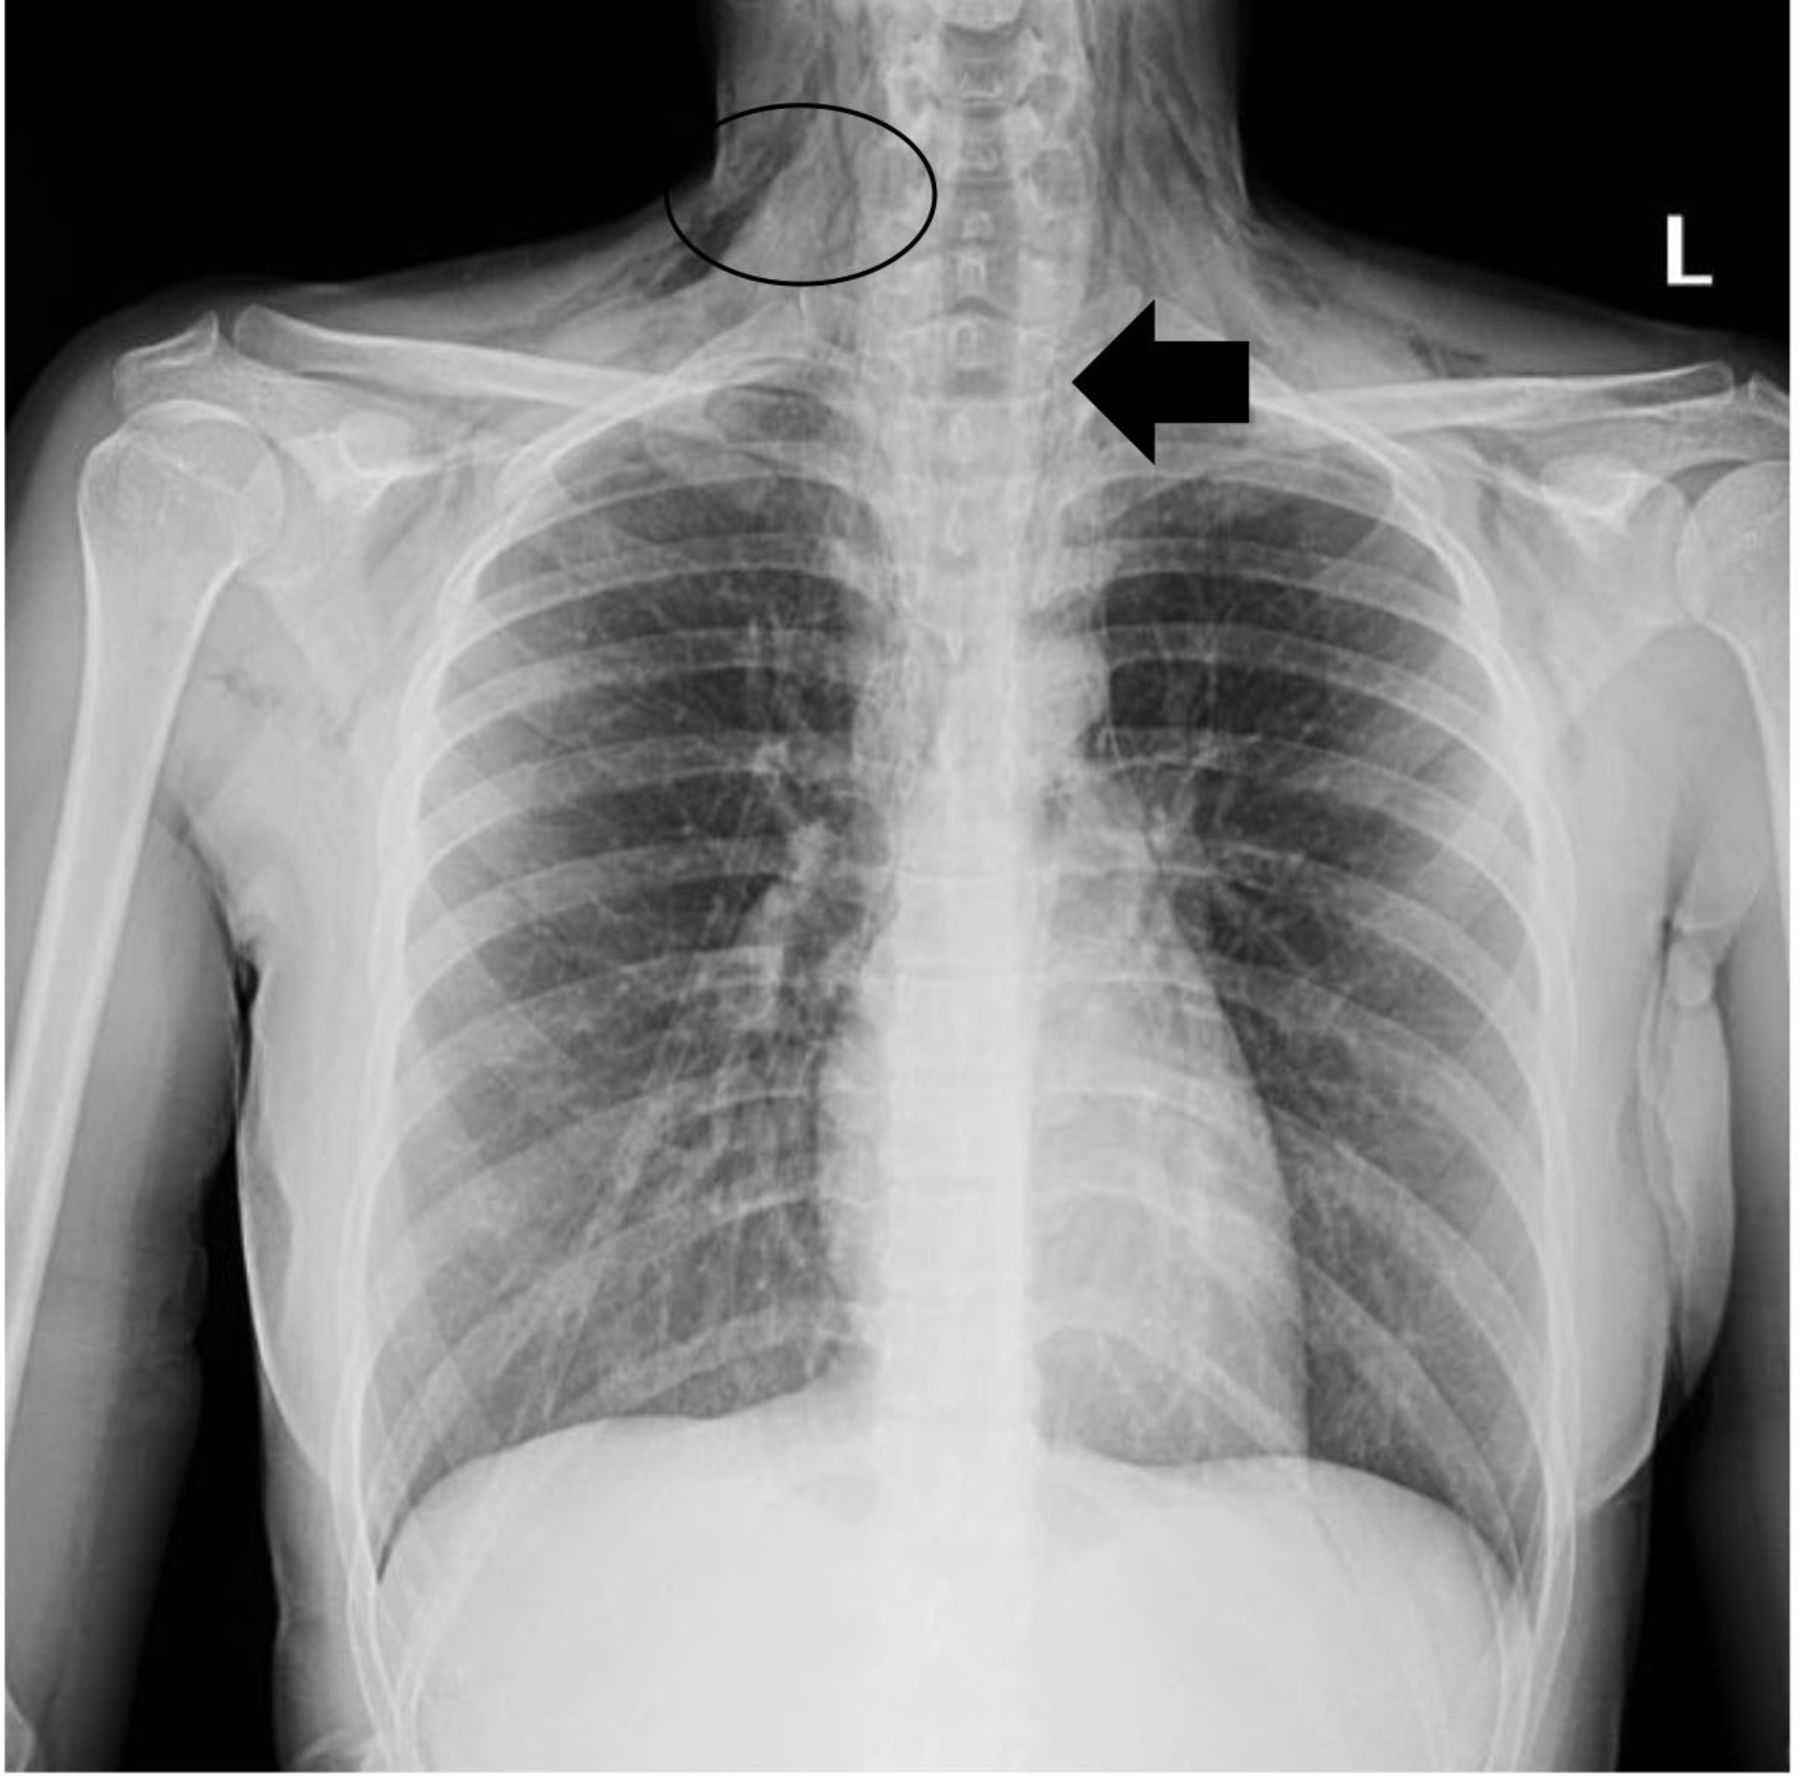

Рентгеновские снимки тератомы средостения: Диагностика и лечение

Раздел: Фотоэссе